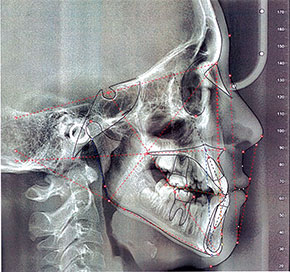

Nuovo software certificato come previsto dalla direttiva MDR 75

I software cefalometrici (software medicali) sono considerati dispositivi medici quindi soggetti al nuovo regolamento europeo MDR 75 che ne prevede la certificazione. Sirio si è prontamente adeguata alla direttiva installando il nuovo software Deltadent in possesso della certificazione come dispositivo medico di classe I m, garantendo così la reciproca sicurezza.Per informazioni: segreteria@sirioradiologiadentale.it